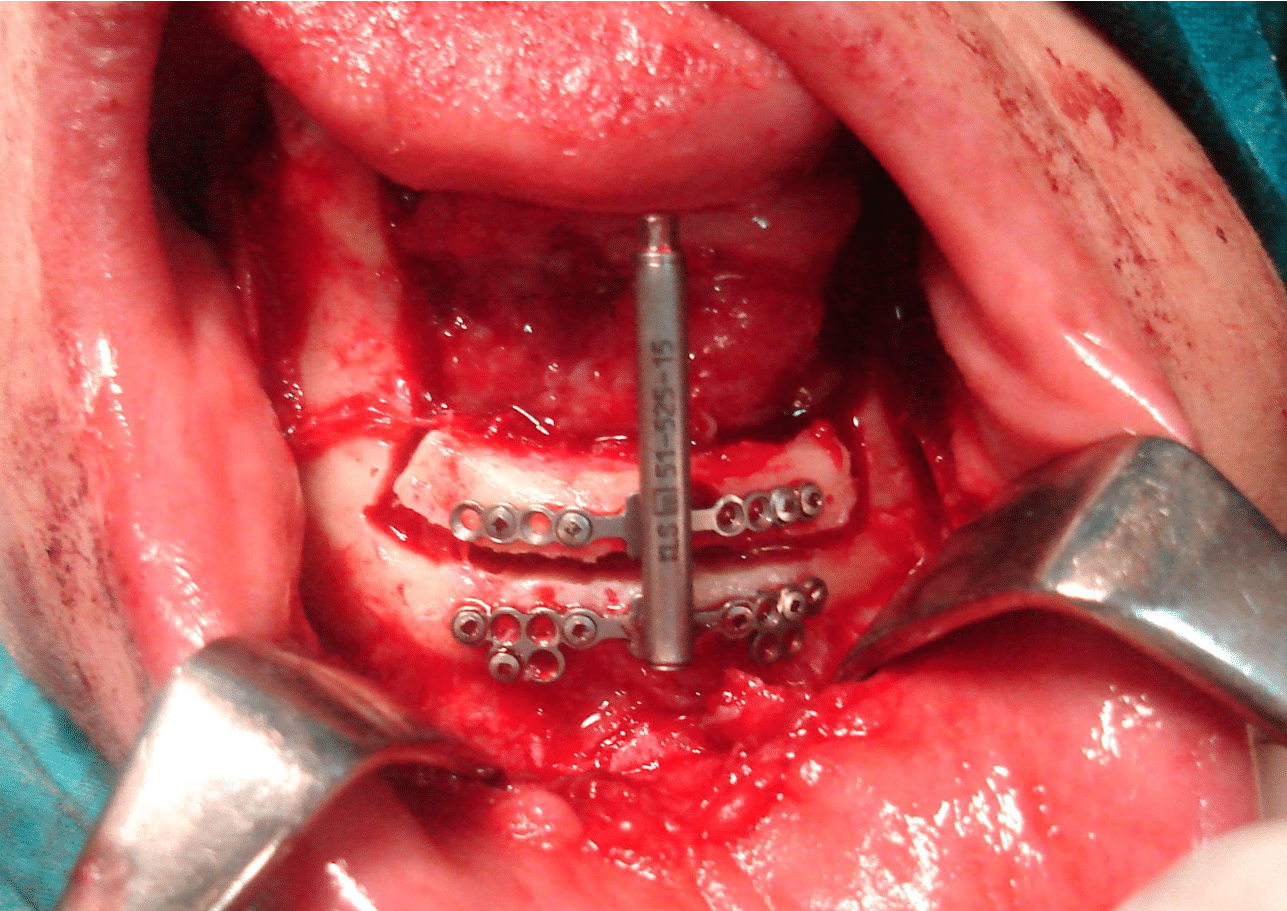

Distraction devices were applied to the bone and adapted to accommodate it plates according to the predetermined distraction vector. Then, devices were screwed by drilling bone using 1.5 mm screws. The osteotomy sites were then marked using surgical bur and the devices were removed. The osteotomy is then completed by using a series of osteotomies on the inferior and superior borders and on the lingual aspect. At this point, activation is attempted to ensure movement of the bone segment (Figure 4). The device is then returned to its starting position. The tissue is carefully closed over the device.

Figure 4 Fixation if the distraction to mandible.